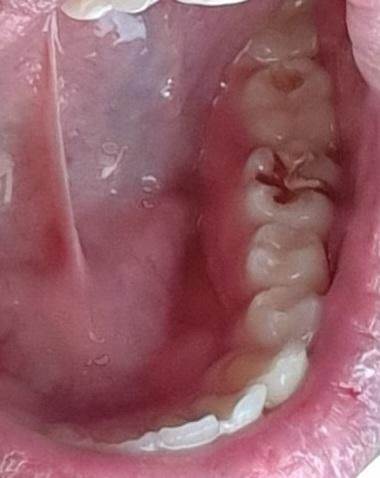

어금니 위쪽에 구멍이 났는데 이거어떠캄??

막 존나 아프진 않는데 양치하다가 보니까 맨 위쪽에 저렇게 구멍이 살짝 뚫려있네요

• 1번 째 사진

정확한건 치과에 가셔서 엑스레이를 찍어보시고 판단을 해야될것같습니다. 충치가 상당히 깊어 보이긴 합니다.

어금니 위쪽에 구멍이 난 경우충치로 보입니다. 방치시에 충치가 더 진행되어 치아 구조가 약해지고, 심한 경우에는 신경까지 손상될 수 있습니다.따라서 가급적 빠른시일내에 치과에 방문하여 상태를 확인하고 치료를 받길 권합니다.

충치가 이미 생겨 치아 법랑질의 구조적 파괴는 일어난 상태같습니다. 충치 치료가 필요해보입니다. 빠른 시일내로 치과 가보세요.